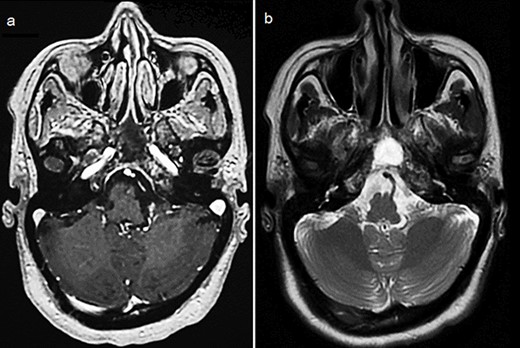

Cerebral computed tomography (CT) revealed a 65-mm hyperdense tumor invading the sphenoid bone and sinus, and eroding the adjacent skull base and clivus. On magnetic resonance imaging (MRI), the tumor appeared isointense on T1 and hypointense on T2-weighted images, showing mild heterogeneous enhancement after gadolinium injection. Local compression and extension to the left cavernous sinus, internal carotid artery, and optic chiasm were observed (Fig. 1).

Cerebral MRI (axial views) showing a 65-mm lesion centered on the sphenoid bone (red arrow) with extension to the internal carotid artery (blue arrow), demonstrating iso-intensity with mild heterogeneous enhancement on T1-weighted (a, b) and hypo-intensity on T2-weighted (c).